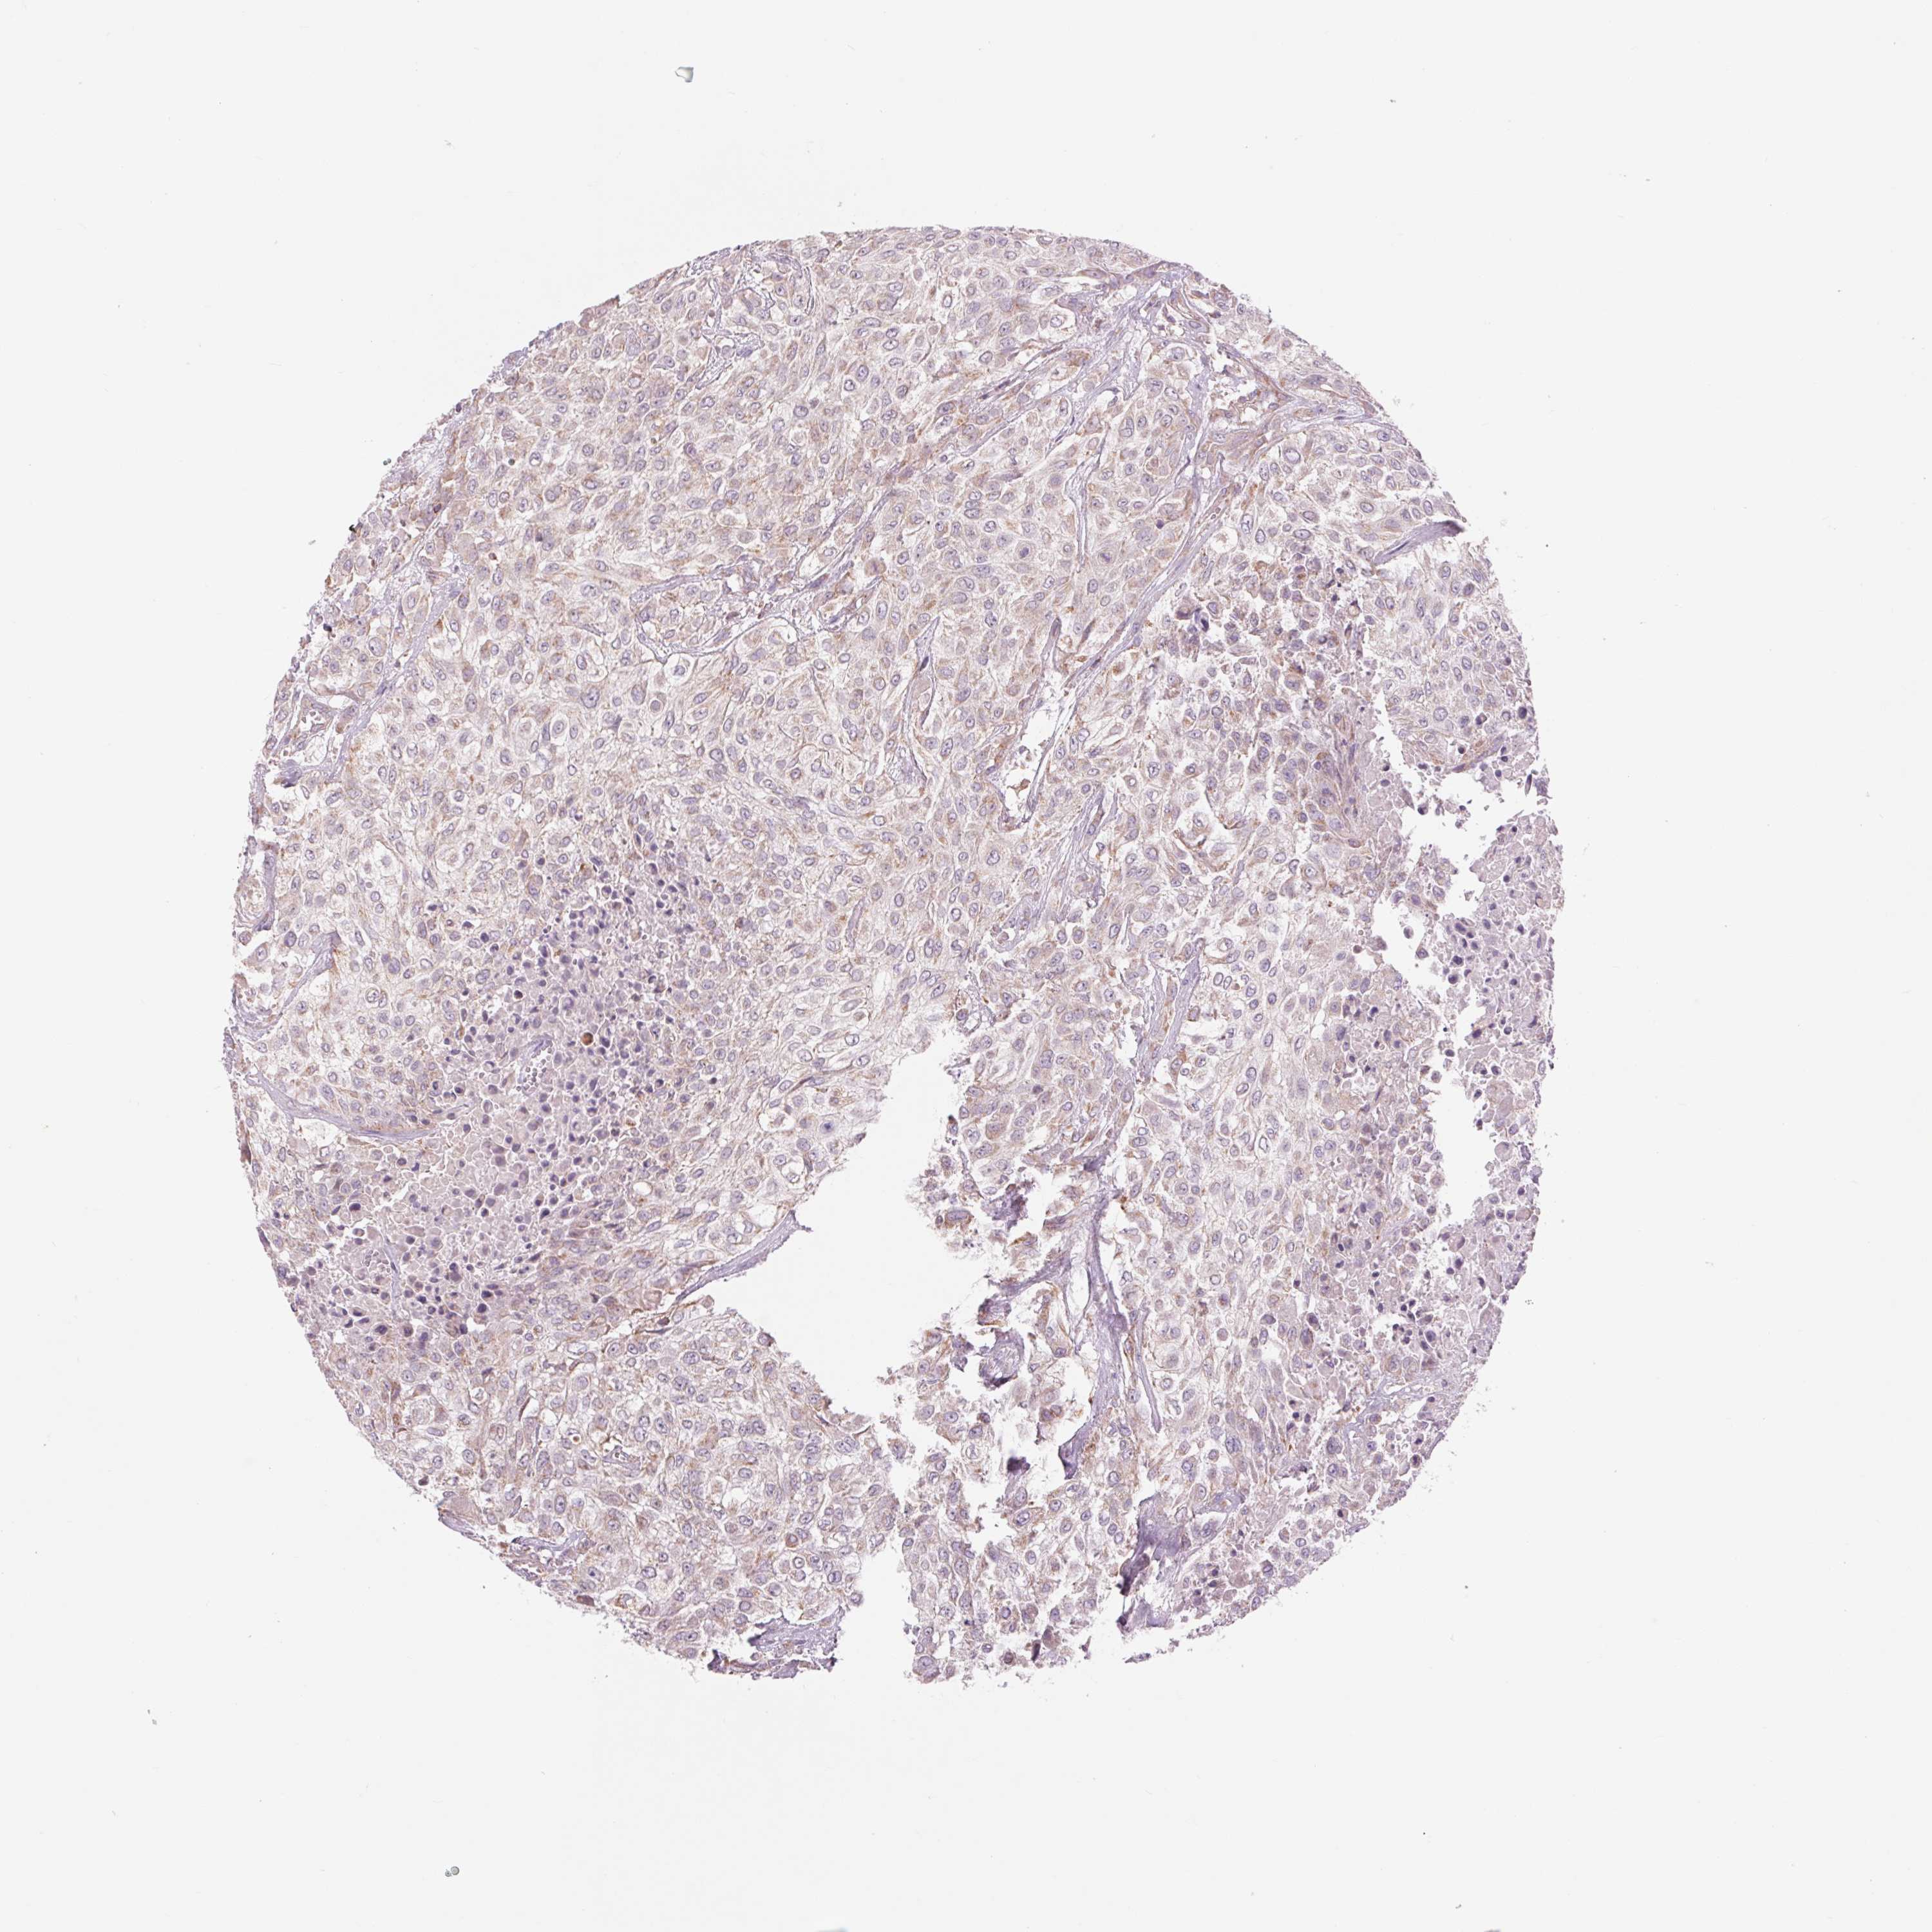

UROTHELIAL CANCER - Protein expressioni

A mouse-over function shows sample information and annotation data. Click on an image to view it in a full screen mode. Samples can be filtered based on level of antibody staining by selecting one or several of the following categories: high, medium, low and not detected. The assay and annotation is described here.

Note that samples used for immunohistochemistry by the Human Protein Atlas do not correspond to samples in the TCGA dataset.

Antibody stainingi

Antibody staining in the annotated cell types in the current human tissue is reported as not detected, low, medium, or high, based on conventional immunohistochemistry profiling in selected tissues. This score is based on the combination of the staining intensity and fraction of stained cells.

Each image is clickable and will lead to virtual microscopy that enables deeper exploration of all samples and also displays staining intensity scores, fraction scores and subcellular localization as well as patient and tissue information for each sample.

Antibody HPA062394

Staining

High

Medium

Low

Not detected

Intensity

Strong

Moderate

Weak

Negative

Quantity

>75%

75%-25%

<25%

None

Location

Urothelial carcinoma, High grade

Urothelial carcinoma, Low grade

Urothelial carcinoma, NOS